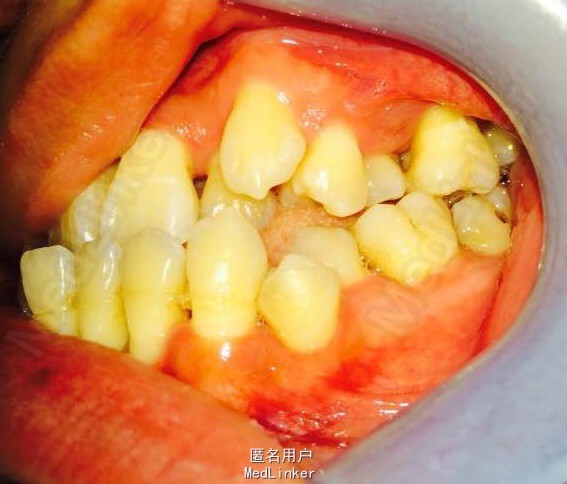

女,23岁,重度侵袭性牙周病,有家族遗传性

讨论:牙周治疗处于维护稳定阶段,下合2—2牙槽骨吸收至根尖1/3水平,是否适合正畸?下个前牙的保留问题